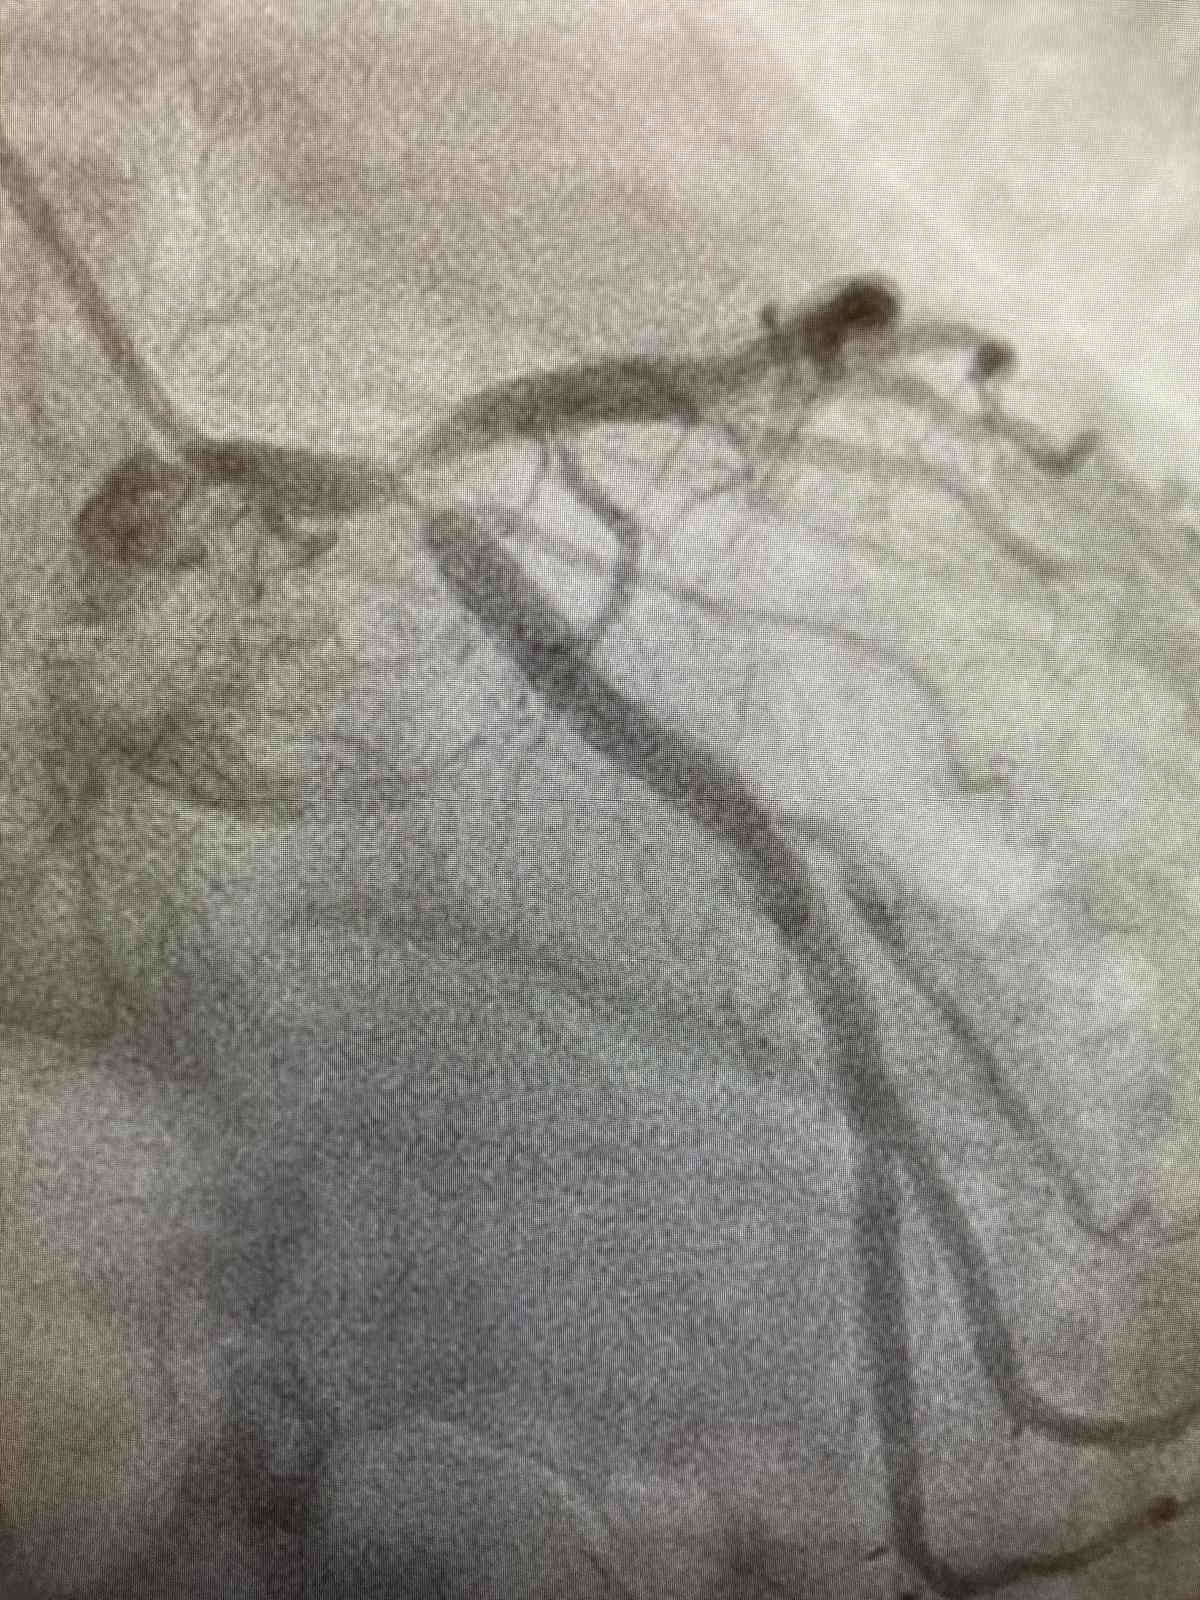

Diyarbakır’da yaşayan ve 3 yıl önce kalp krizi geçirip damarlarına stent takılan Mehdi Tekin, dün sahur yaptığı sırada fenalaştı. Ailesinin haber vermesi üzerine olay yerine 112 acil sağlık ekibi yönlendirildi. Diyarbakır Memorial Hastanesine kaldırılan ve kan değerleri normal çıkan Tekin’in kalp krizini düşündüren şikayetlerinin olması üzerine doktorlar anjiyo yapma kararı aldı. Tekin’e el bileğinden girilerek yapılan anjiyo yapıldı. Kalbin en önemli komşu iki damarının çatal bölgesi tıkalı olan Tekin, yapılan anjiyo ile sağlığına kavuştu.

40 yaşından sonra herkesin bir kalp krizi geçirme ihtimalinin olduğunu kaydeden Doç Dr. Aydın, "Muhakkak yılda en az bir defa kardiyoloji muayenesi olunması gerekir. 45 yaşındaki hastamız göz kararması, baş dönmesi nedeniyle hastanemiz acilinde başvurmuş yapılan tetkikler normal çıkmıştı. Hastamız yaklaşık 3 yıl önce kalp krizi geçirmiş, stent takılmış. Kan değerleri normal çıkmış olmasına rağmen kalp krizini düşündüren şikayetlerinin olması nedeniyle anjiyo yapılmasına karar verdik ve bunun sonucunda kalbin en önemli komşu iki damarın çatal bölgesinde tıkalı olduğunu gördük. El bileğinden kısa sürede yaklaşık bir saat süren bir işlemle damarlar sağlıklı bir şekilde açıldı. Şu an hastamızı sağlıklı bir şekilde taburcu ettik" diye konuştu.